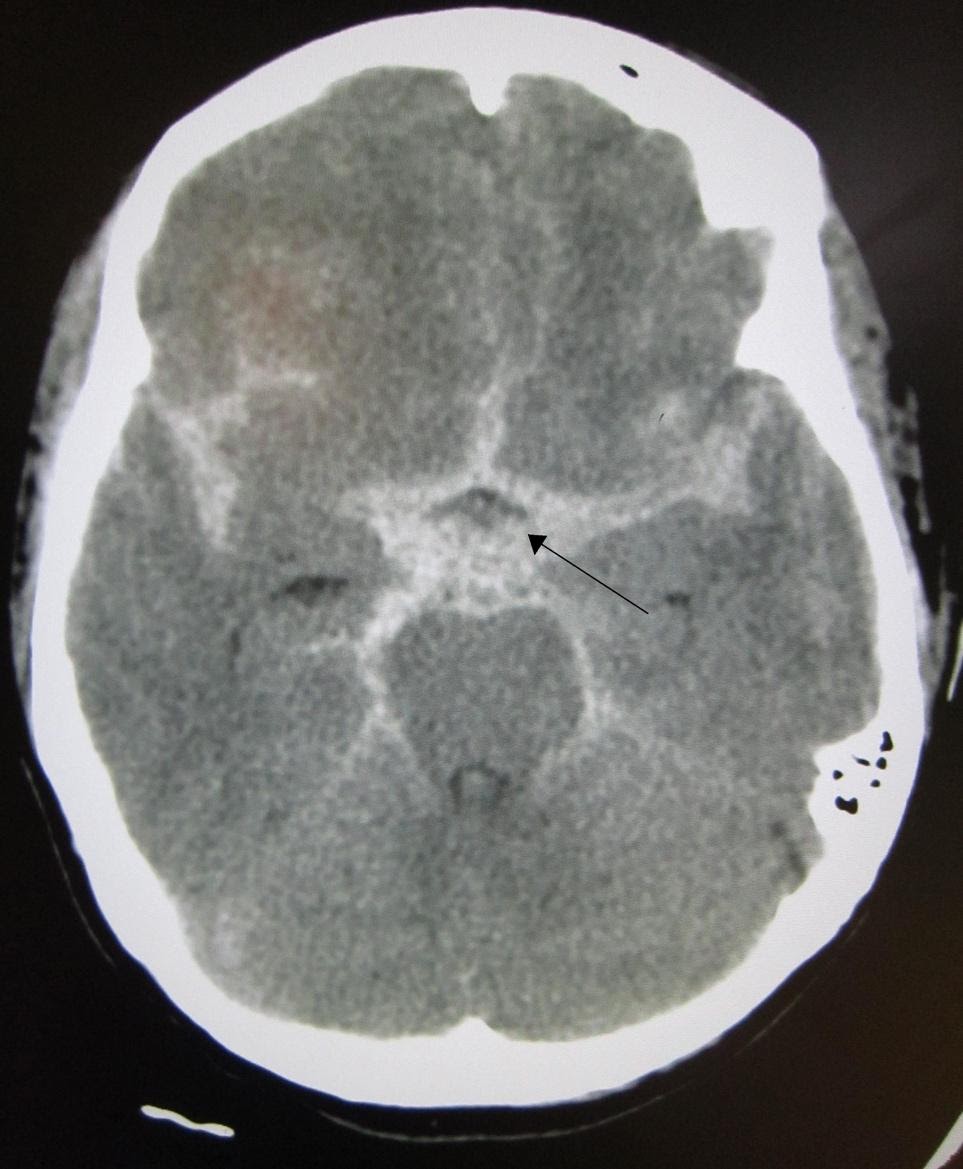

- Subarachnoid Hemorrhage

A subarachnoid hemorrhage appears as blood in the ventricles, sulci, and cisterns on CT. An example of a CT scan showing SAH is shown in Figure 1. The overall sensitivity of CT for subarachnoid hemorrhage is best within the first 6 hours. Sensitivity declines with time, particularly with detection of smaller bleeds.

Image 1. CT Scan showing Subarachnoid Hemorrhage (SAH). Arrow added demonstrating area of SAH. Image courtesy of : https://commons.wikimedia.org/wiki/File:SAH1.JPG. This file is licensed under the Creative Commons Attribution-Share Alike 3.0 Unported license.